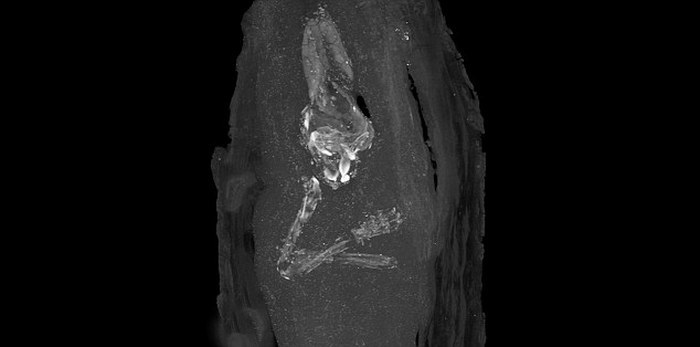

Рентгеновское изображение верхних конечностей и черепа плода. Музей Фицуильяма в Кембридже

Открытие было сделано специалистами в музея Фицуильяма в Кембридже. Они осмотрели деревянный гроб, который был передан музею археологами еще в 1907 году. Гроб крошечного размера (всего 44 сантиметра в длину) был найден во время раскопок в Гизе в 1907 году, а захоронение датируется примерно 664 - 525 годами до н.э.

Кураторы музея Фицуильяма сделали свое удивительное открытие, проводя исследование для выставки под названием "Смерть на Ниле: Раскрытие секретов посмертия Древнего Египта". При этом они использовали так называемые "неинвазивные технологии", чтобы заглянуть внутрь "экстраординарной археологической находки" и просвечивали ее рентгеновскими лучами.